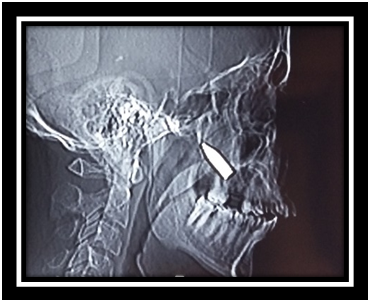

Gas Gangrene in the Neck Caused by an Odontogenic Infection- A Case Report